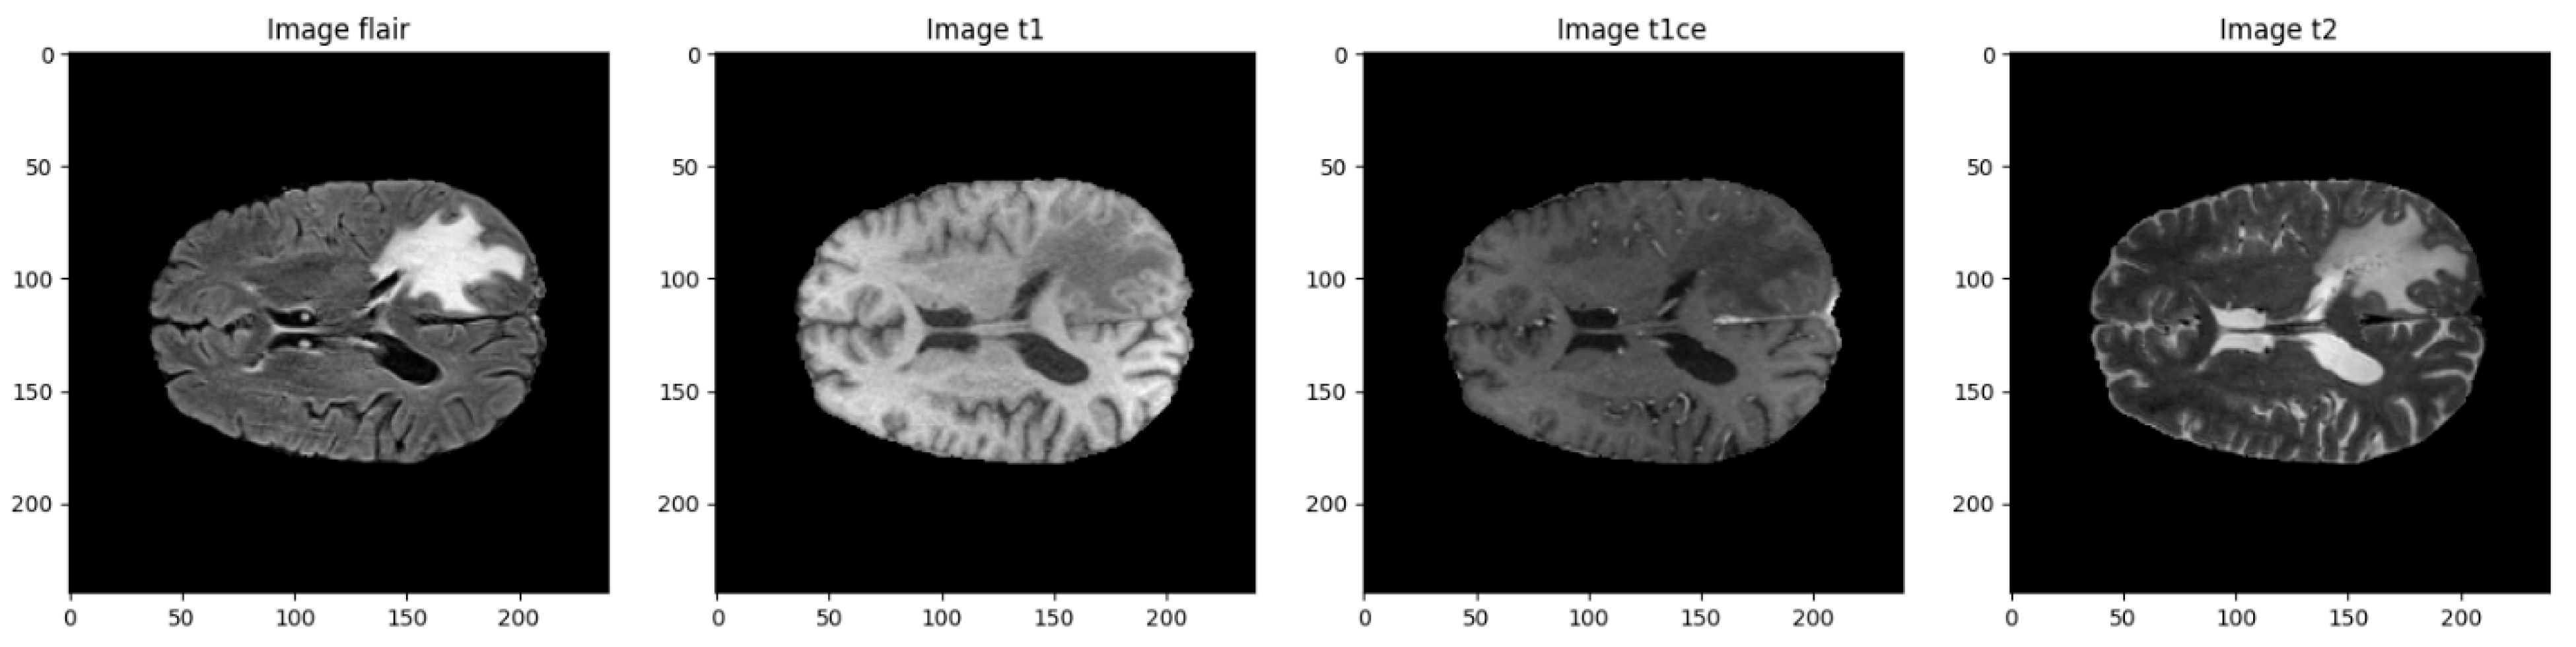

Input Modalities

- Input Shape: Each input consists of two channels—FLAIR and T1CE—resulting in a shape of (128, 128, 2).

| Modality | Description |

|---|---|

| T1 | T1-weighted structural MRI |

| T1CE | T1-weighted with contrast enhancement (gadolinium) |

| T2 | T2-weighted imaging, useful for fluid detection |

| FLAIR | Fluid-Attenuated Inversion Recovery, suppresses CSF to highlight lesions |